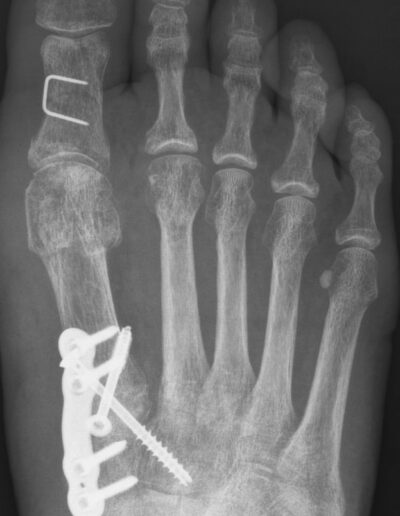

Mehr InformationenExemplarische Röntgenbilder vor und nach OP bei Hallux valgus

Es wurden bisher gut 100 verschiedene OP-Techniken publiziert um die Hallux valgus Fehlstellung zu beheben. Aus der Menge der Verfahren sollte sich ein Operateur nur weniger Techniken bedienen, die er sicher beherrscht und so zum Einsatz kommen. Das OP-Verfahren sollte individuell an die Begebenheiten des Fußes angepasst werden. Hierzu ist eine persönliche Untersuchung des ganzen Fußes durch den Operateur erforderlich.

Welches OP-Verfahren dann bei Ihrer OP zum Einsatz kommt und was die Gründe hierfür sind erkläre ich Ihnen persönlich nach meiner Untersuchung Ihres Fußes und anhand der Röntgenbilder. Eine Kernspintomographie ist in der Regel nicht erforderlich. Der geplante Eingriff kann ambulant oder kurzstationär durchgeführt werden. Eine kurze, oberflächliche Vollnarkose wird dafür erforderlich. Ich begleite Sie persönlich-angefangen von der Vorbereitung einer OP bis zum Ende der Nachbehandlung detailliert und individuell angepasst.